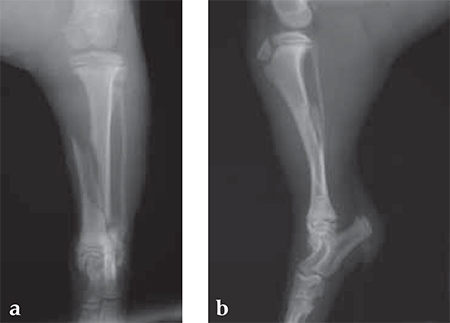

A 12-week-old Yorkshire Terrier, 1.3 kg

(Case provided by Alessandro Piras, Banbridge, Northern Ireland)

Small Bones, Small Plates: Clinical Application of Mini LCP